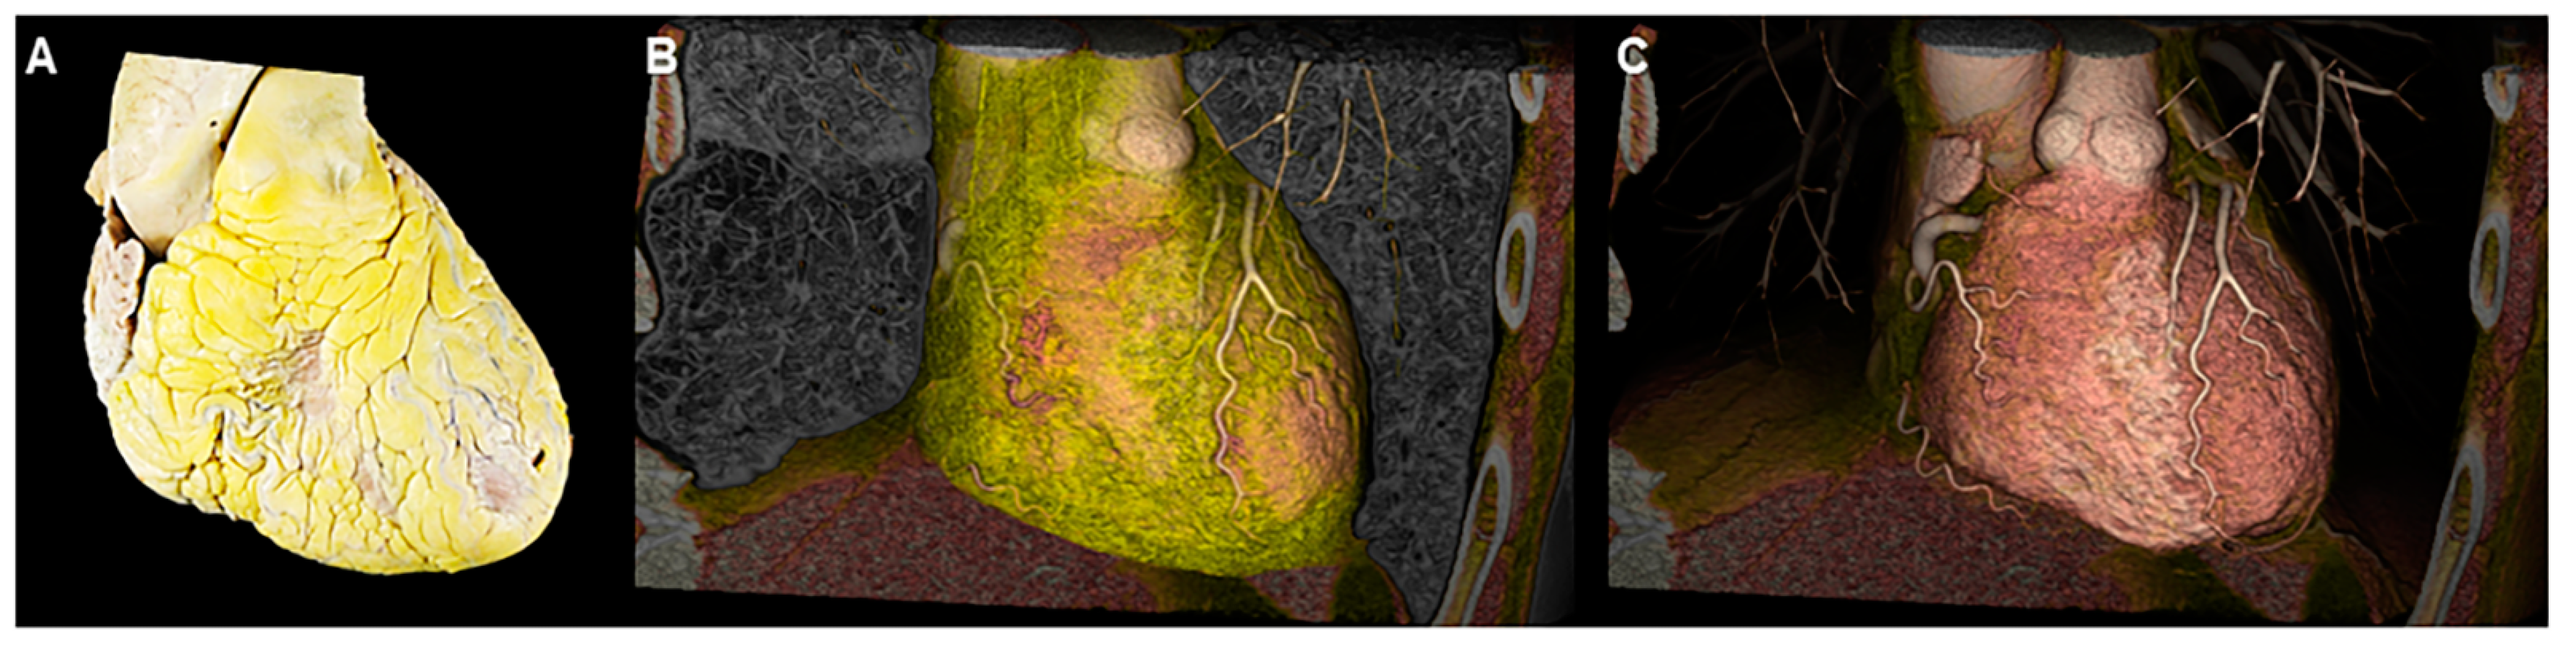

2. The Concept of Three-Dimensional Imaging Using the Volume-Rendering Method

3. The Advantage of the Virtual Dissection Compared to Conventional Real Dissection